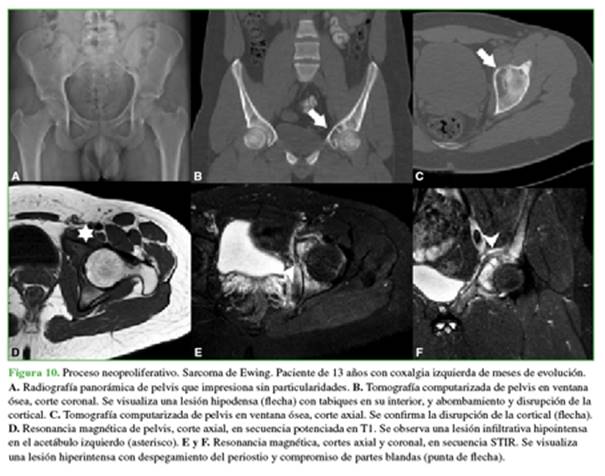

Los diagnósticos diferenciales más frecuentes son procesos neoplásicos (Figura 10), infecciones u otros procesos granulomatosos (tuberculosis).